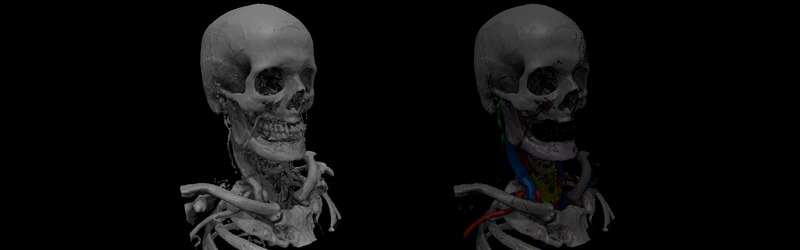

Cross Sectional Anatomy Of The Neck

Cross Sectional Anatomy Of The Neck

Mri Neck Anatomy Free Mri Axial Neck Cross Sectional Anatomy

Mri Neck Anatomy Free Mri Axial Neck Cross Sectional Anatomy